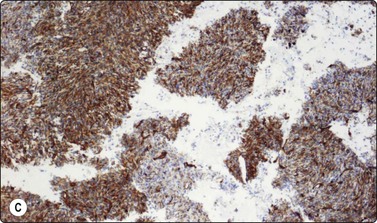

Merkel cell carcinoma (neuroendocrine carcinoma of skin) (Fig. 14.17, and see Fig. 5.23)61,62

image

Fig. 14.17 Merkel cell carcinoma

(A) Poorly cohesive cells; nuclear pleomorphism and some molding, scanty blue cytoplasm resembling lymphoid cells (MGG, HP); (B) Cellular smear of dispersed small cells with round, dark nuclei (Pap, HP); (C) Dot-like positive staining with CAM5.2 (immunostaining, HP).

Criteria for diagnosis

Cell-rich smears of mainly dispersed small neoplastic cells,

Fragile, scanty, blue (MGG) cytoplasm; high nuclear : cytoplasmic ratio; many stripped nuclei,

Clustered cells may show nuclear molding and rosette-like grouping,

Round or ovoid, mildly to moderately irregular hyperchromatic nuclei with inconspicuous nucleoli,

Mitoses frequent,

Lymphoid globules (lymphoglandular bodies) absent,

Dot-like paranuclear staining for cytokeratin; chromogranin usually positive.

Primary neuroendocrine carcinoma of skin is an uncommon neoplasm, mainly seen in elderly patients and most often in the head and neck. It is locally aggressive and often metastasizes to regional lymph nodes. Clinically and cytologically, Merkel cell tumor can be difficult to distinguish from non-Hodgkin lymphoma when it presents as lymphadenopathy without an obvious primary, as is often the case (see Chapter 5).

Page 379

Smears are usually highly cellular. The cells are mainly dispersed but some are clustered or form single files with nuclear molding and sometimes rosette-like groups. The main differential diagnoses are lymphoma and metastatic small cell carcinoma. Amelanotic melanoma may also be considered. The absence of lymphoid globules in the background and subtle differences in nuclear chromatin help in this distinction. Staining for CAM5.2, CK7 and CK20 demonstrates characteristic dot-like intracytoplasmic deposits in the tumor cells (Fig. 14.17C), and staining for neuroendocrine markers is usually positive. Electron microscopy shows well-demarcated whorls of cytoplasmic filaments.